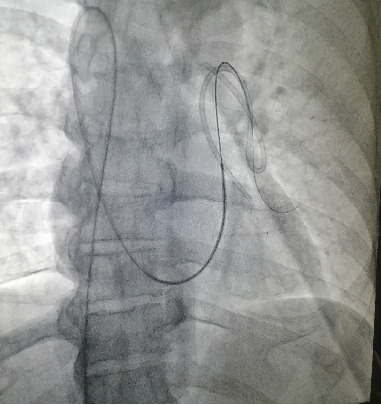

植入式皮下化疗孔是肿瘤化疗的常规载体。自发的导管脱位和导管栓塞是手术中罕见的并发症。在此,我们报告我们的经验,病人表现为自发性脱位和导管迁移到肺动脉。家族性腺瘤性息肉病合并右结肠腺癌患者行全直结肠切除术,经颈内静脉放置化疗孔,进行FOLFOX辅助化疗。被夹住的导管由介入心脏病专家通过经皮回收成功处理。

Implantable subcutaneous chemoports are routinely employed for delivering chemotherapy in oncology. Spontaneous catheter dislodgement and embolization of the catheters are rare complications of the procedure. Herein, we report our experience with a patient presenting with spontaneous dislodgement and migration of the catheter to the pulmonary artery. The patient having familial adenomatous polyposis with adenocarcinoma of the right colon underwent total proctocolectomy and had placement of the chemoport through the internal jugular vein for adjuvant FOLFOX chemotherapy. The entrapped catheter was successfully managed by percutaneous retrieval by an interventional cardiologist.